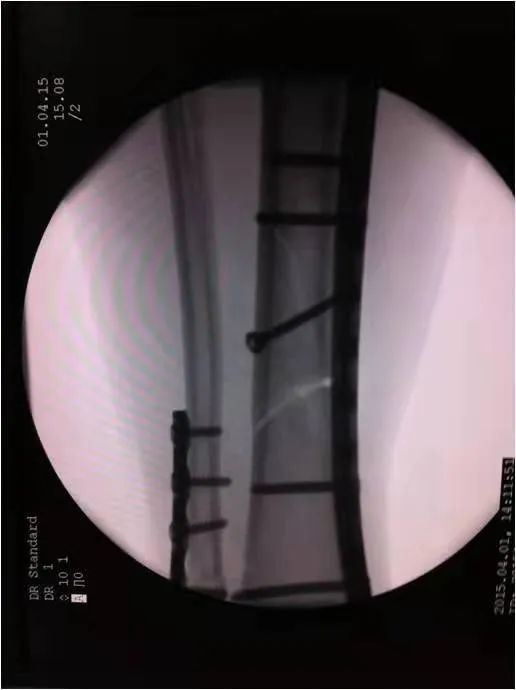

如采用傳統(tǒng)手術(shù)需大范圍剝離軟組織,手術(shù)切口在18公分,損傷面大,影響骨折愈合。經(jīng)過科內(nèi)術(shù)前討論后與患者及家屬溝通后,呂國福主任決定行小切口微創(chuàng)鈦板植入內(nèi)固定手術(shù)治療,術(shù)中植入內(nèi)固定物并剝離軟組織,此方法對周圍皮膚破壞小,手術(shù)切口最小僅0.5公分,極大降低皮膚壞死及后期出現(xiàn)骨不連發(fā)生幾率,從而達到解剖復位。

在急診科,檢驗科,麻醉科共同努力下,僅用一小時完成整個手術(shù),術(shù)中出血量少、過程順利,手術(shù)非常成功。術(shù)后,呂國福主任數(shù)次查房,仔細查看患者的傷口愈合情況,關(guān)心患者的心理狀態(tài),為患者樹立信心,鼓勵患者進行功能鍛煉。